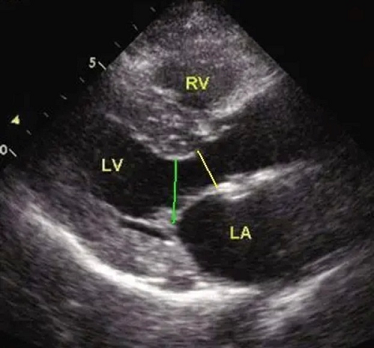

超声心动图:胸骨旁左室长轴切面可见左室壁明显肥厚,以室间隔和左室前壁肥厚为著。乳头肌水平室间隔最厚处约23.3mm,位于主动脉瓣下21mm处,前壁室壁厚21.5mm,侧壁室壁厚18.1mm,后壁室壁厚17.5mm。肥厚心肌运动僵硬。

术前超声心动图